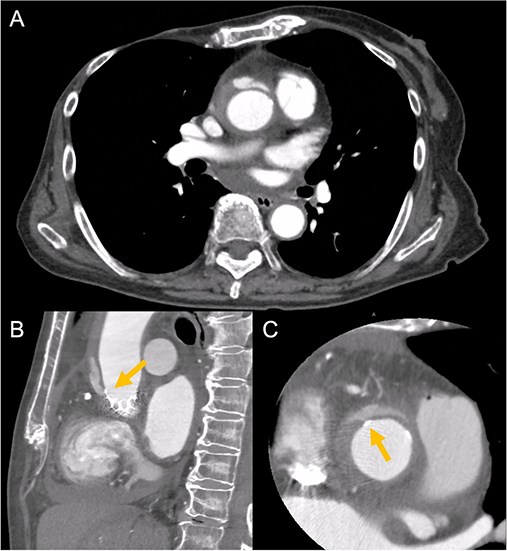

An 88-year-old woman with severe symptomatic AS (aortic valve area: 0.40 cm2; peak velocity: 4.9 m/s; mean pressure gradient: 56 mm Hg) and ischemic heart disease with severe stenosis in the proximal segments of both the left anterior descending (LAD) coronary artery and circumflex arteries was referred from another hospital for invasive treatment. The patient was taking edoxaban 30 mg, nifedipine 20 mg, perindopril 4 mg, and candesartan 8 mg for the treatment of atrial fibrillation and hypertension. The patient’s perioperative risk was high, with a Society of Thoracic Surgeon (STS) score of 9.31% and Logistic EuroSCORE of 23.11%. Following discussion with the heart team, we decided to perform TAVI before coronary revascularization, with percutaneous coronary intervention (PCI) planned postoperatively. We evaluated the aortic valve complex using contrast-enhanced computed tomography (CT), which revealed a narrow sinotubular junction (STJ) with small calcifications measuring 20.6 × 22.3 mm (Fig. 1). TAVI was performed via a transfemoral approach under local anesthesia and sedation. A 23-mm SAPIEN 3 THV (Edwards Lifesciences, Irvine, CA, USA), which provides better coronary access due to its shorter frame length and relatively larger cell size, was deployed without prior balloon aortic valvuloplasty. To minimize the risk of injury to the STJ, the THV was deployed with a reduced balloon volume (−1 cc), and post-dilatation was conducted with the balloon positioned toward the left ventricular side (Fig. 2). Postoperatively, the patient’s blood pressure stabilized with rest and a reduced-sodium diet, allowing modification of the antihypertensive therapy to sacubitril/valsartan 100 mg alone. Additionally, aspirin 100 mg was added to ongoing edoxaban therapy for the planned PCI. The postoperative course was uneventful, and the patient was subsequently discharged. However, on day 4 after discharge, the patient experienced acute chest discomfort. Blood tests, electrocardiography, and transthoracic echocardiography revealed no significant changes from the time of discharge, and the patient was sent home as the symptoms gradually improved. On day 7 after discharge, contrast-enhanced CT—originally scheduled as a preoperative assessment for PCI at the referring hospital— incidentally revealed a localized dissection of the ascending aorta. The entry point of the dissection was located at the STJ extending toward the THV stent frame, consistent with Stanford AAD associated with TAVI (Fig. 3). The patient was transferred to our hospital and underwent surgery, including aortic valve replacement, ascending aorta replacement, and coronary artery bypass grafting (left internal thoracic artery to the LAD and saphenous vein graft to the obtuse marginal branch). Intraoperatively, removal of the THV and calcified STJ tissue revealed a pinhole-like intimal defect, which was continuous with a hematoma within the media and identified as the entry point of the dissection. Macroscopic pathological examination of the resected ascending aorta also confirmed the presence of a small intimal defect (Fig. 4). This intimal injury was therefore considered to have resulted from compression of the calcified tissue caused by THV implantation. After ~1 month of rehabilitation, the patient was discharged in an ambulatory state on postoperative day 30.

Contrast-enhanced CT on day 7 after discharge shows an AAD in the ascending aorta (A) with the entry point at the STJ extending toward the THV stent frame, suggesting an AAD associated with TAVI (B and C, arrow).